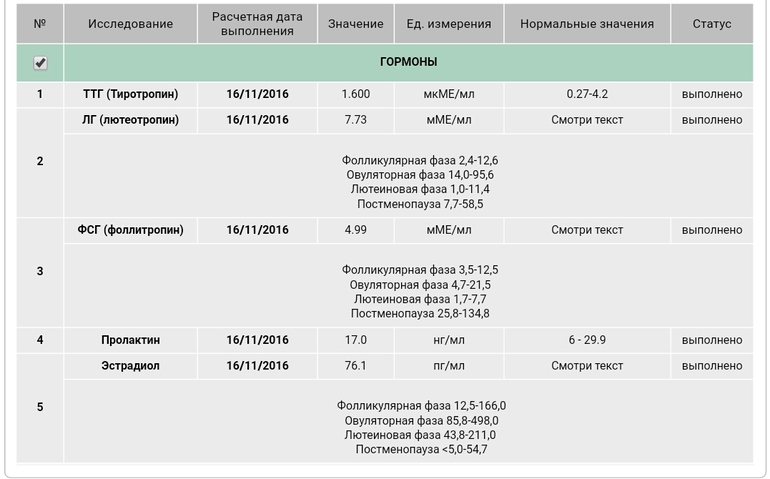

В общем ниже УЗИ, гормоны на 5 ДЦ и график БТ. Что скажете?

Судя по соотношению ЛГ/ФСГ овуляция, действительно ранняя

Похоже на 7 дц, но почему вчера так упала бт... Можно было б еще предполржить, что вчера, но по гормонам видно, что уже вторая фаза. А узи и гормоны когда сдавали? И как на 7дц як могла перезреть?) Падение вчера вдруг ИЗ?

Гормоны на 5дц, узи на 12дц.